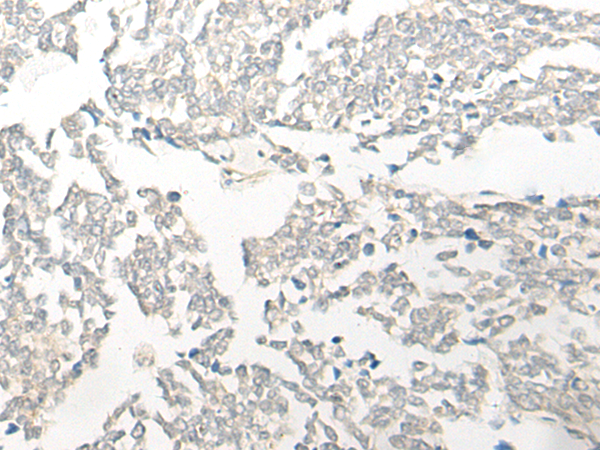

分类: 科研抗体货号: P09616别名: DEM1; Exo V; hExo5; C1orf176应用: IHC反应种属: Human, Mouse